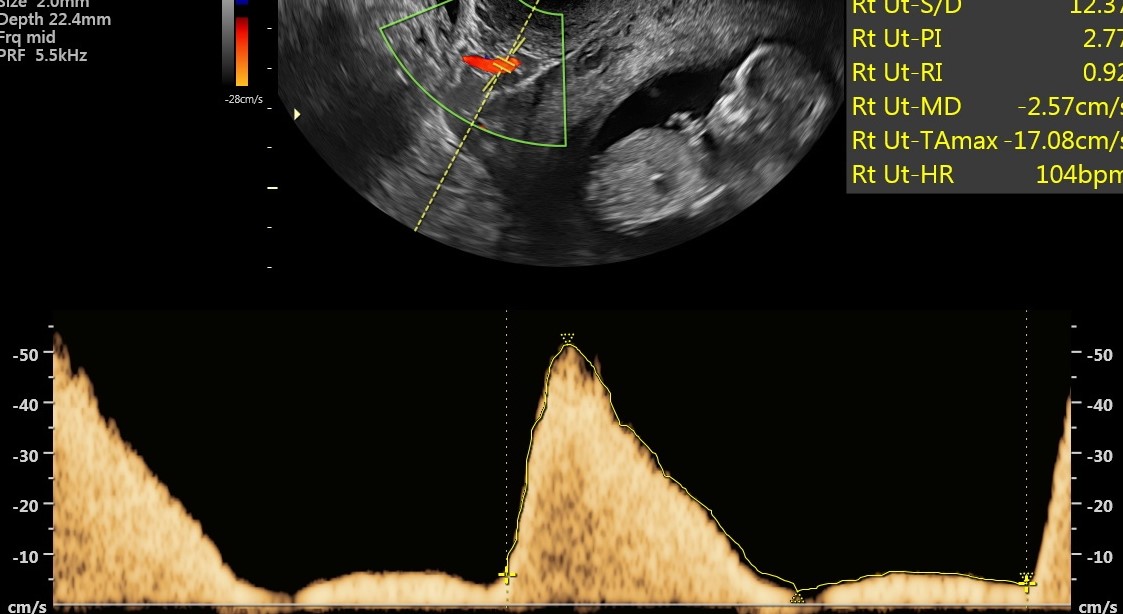

Nieprawidłowe przepływy w tętnicy macicznej w czasie ciąży, fot. USK-2

Kobietom objętym programem PRENATALPROJEKT wykonywane jest w 1. trymestrze badanie USG, mierzone jest ciśnienie oraz badane są trzy substancje, które pozwalają zdiagnozować funkcjonowanie łożyska i wykryć ww. patologie. Standardowe badania prenatalne obejmują badanie dwóch substancji i nie dają one wystarczająco miarodajnych i pewnych wyników co do prawidłowości funkcjonowania łożyska. W 2. trymestrze ciąży wykonywane jest już samo USG oraz badane ciśnienie. W przypadku wykrycia nieprawidłowości ciężarna zostaje objęta szczególną opieką i monitoringiem. W specjalnie utworzonej aplikacji, którą może pobrać na telefon i z której korzysta także jej ginekolog położnik, podaje mierzone kilka razy dziennie ciśnienie oraz wagę. Lekarz badań prenatalnych, biorący udział w programie decyduje o podjęciu leczenia. W przypadku niewydolności łożyska jest nim podanie odpowiedniej dawki aspiryny. Kobieta przyjmuje ją pod kontrolą lekarza do 36. tygodnia ciąży, który określany jest jako bezpieczny dla rozwoju dziecka, a rozwiązanie ciąży nie stanowi dla niego już takiego ryzyka.